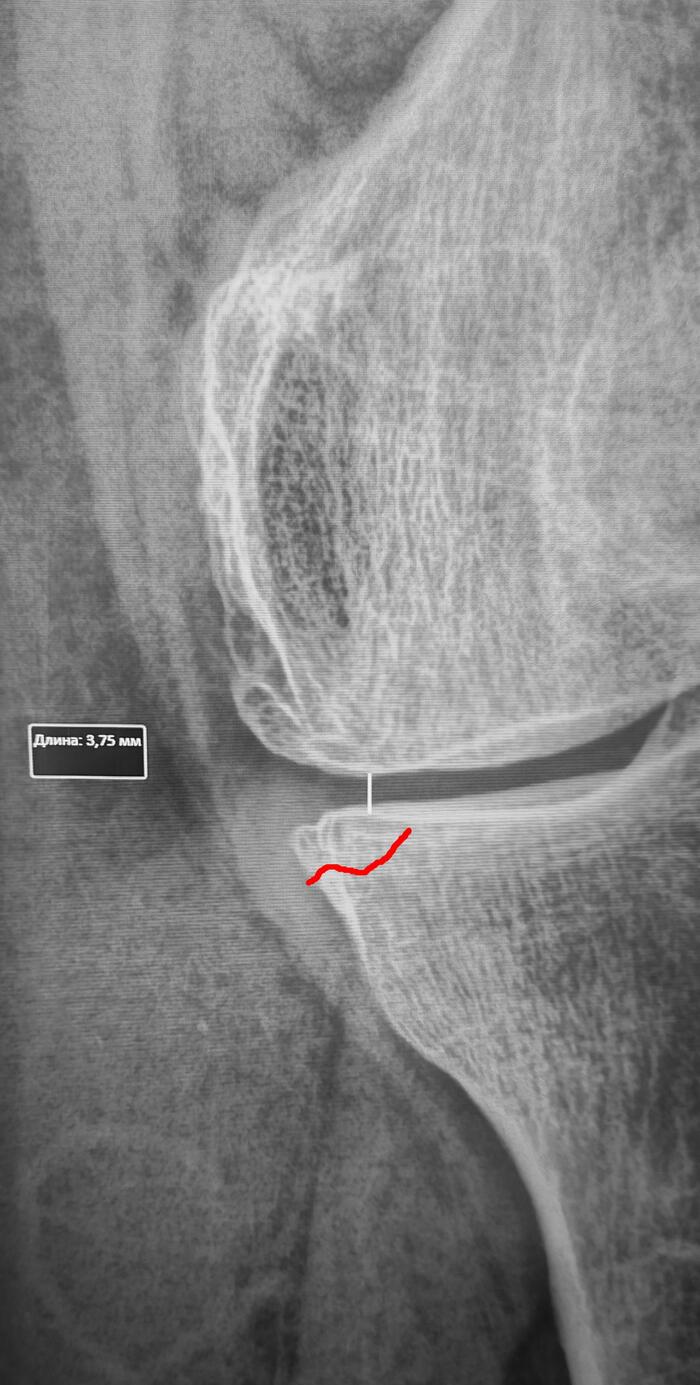

Стресс-перелом мыщелка большеберцовой кости

Стресс-перелом – это трещина в кости, вызванная повторяющимися нагрузками, а не единичным травматическим воздействием.

Косая линия просветления костной ткани в медиальном мыщелке левой б/б кости, сужение рентгенологической щели левого коленного сустава в медиальных отделах до 3.7,краевые остеофиты, субхондральный склероз суставной поверхности, заострение, деформация межмыщелковых возвышений. Заключение: Стресс-перелом медиального мыщелка левой большеберцовой. Гонартроз слева 2 ст.

Категория годности по ст.85(Временные функциональные расстройства костно-мышечной системы, соединительной ткани, кожи и подкожной клетчатки после лечения болезней, ранений, травм, отравлений и других воздействий внешних факторов) Г-временно не годен к военной службе сроком на 3 мес., с последующим оформление с диагнозом гонартроз 2 ст. по ст.65в-В(ограниченно годен к в/сл).